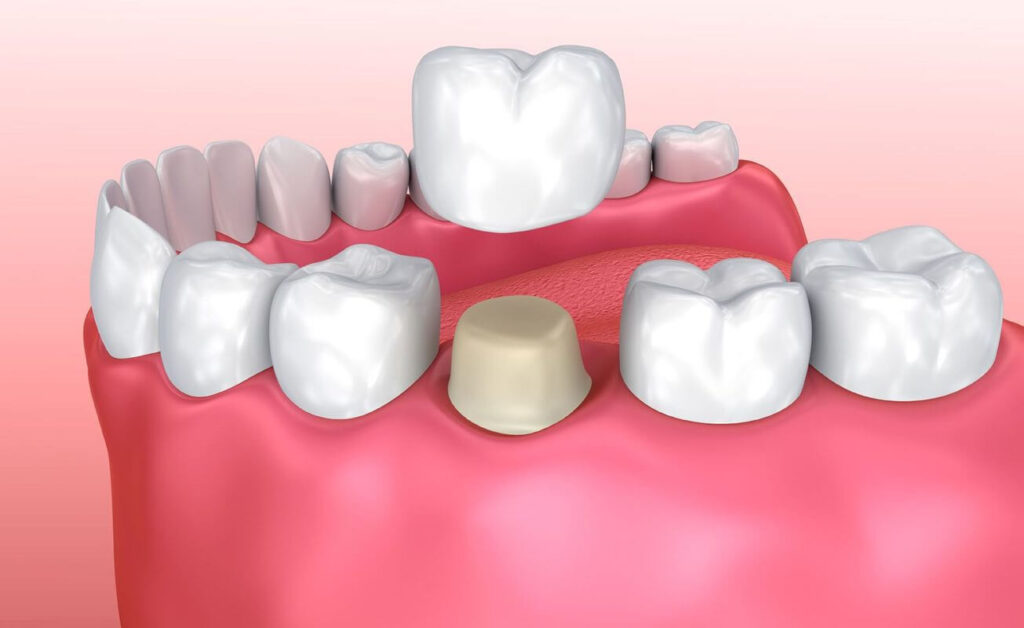

A ceramic crown is the easiest way to improve your smile. It acts like a cap for a broken tooth, covering it. They are made in such a way that the artificial teeth look real, making the smile appear natural. Crowns straighten the teeth, giving the entire smile a clean and beautiful appearance. They are strong and long lasting. If you also want to get this treatment from a professional doctor, you can visit Envisage Dental Clinic today. It is the best dental clinic in Noida Sector 50.